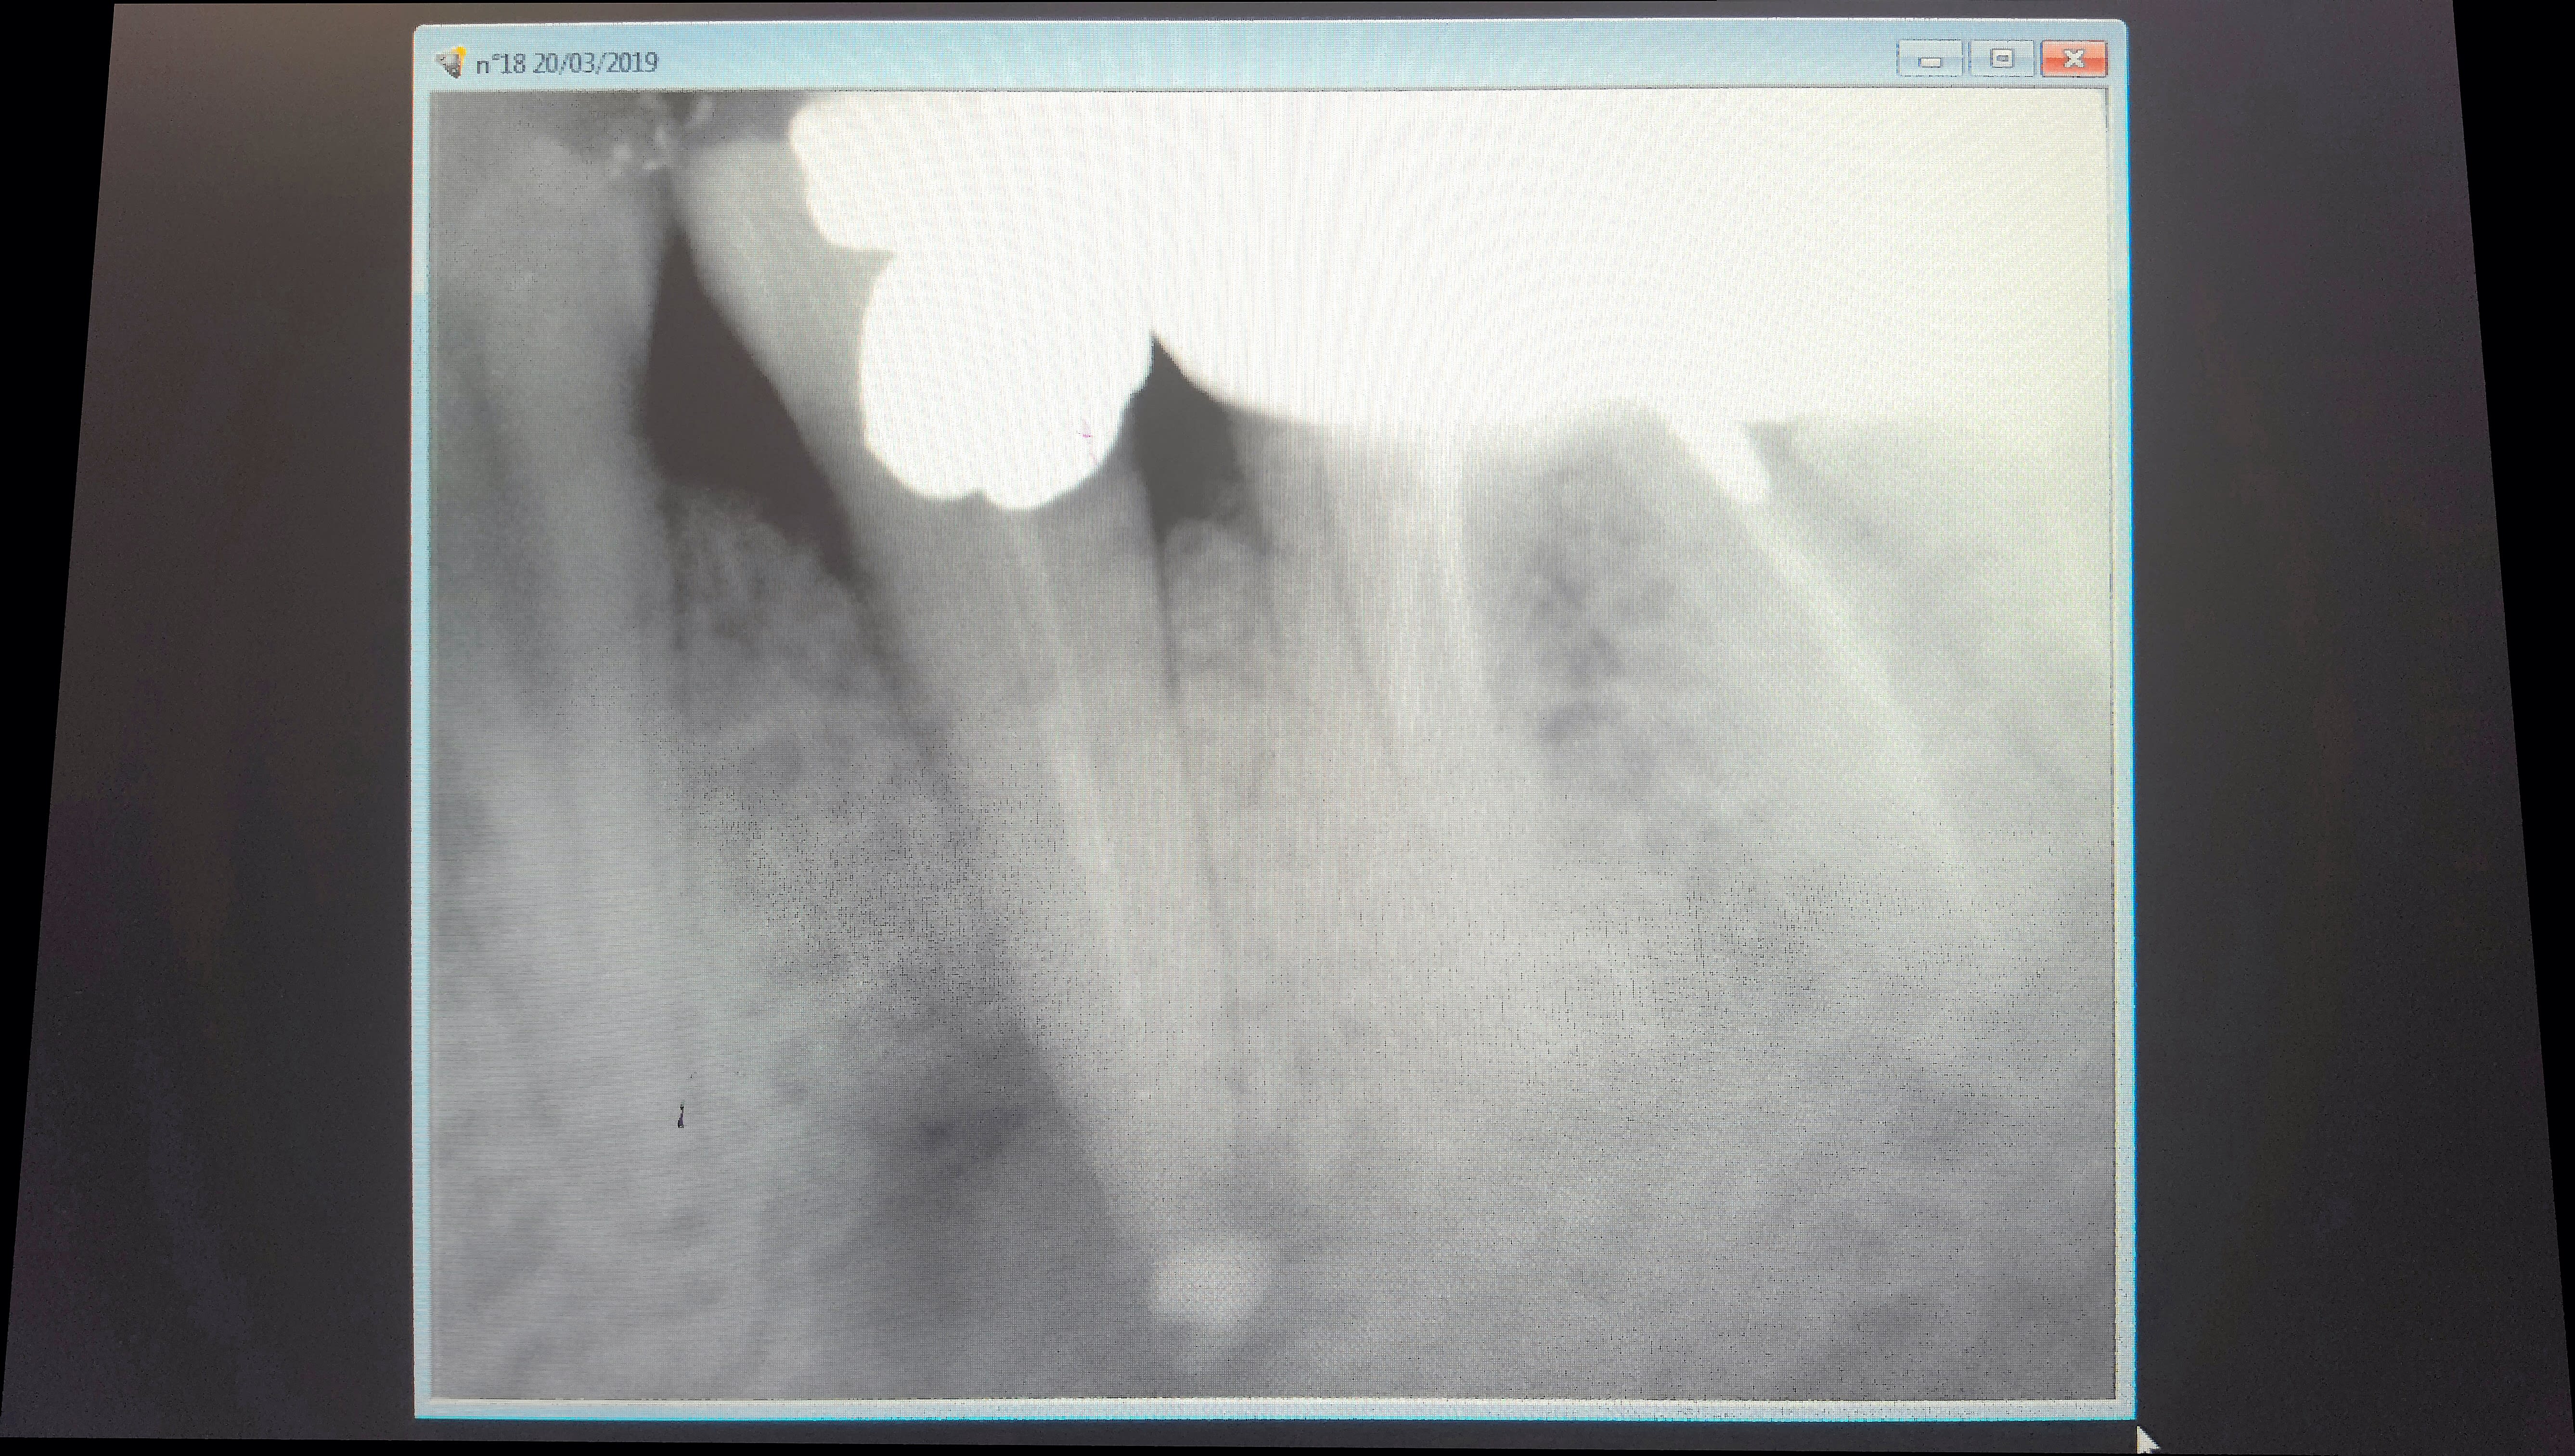

Je fais la radio de contrôle et je vois un gros dépassement d'hyca ,juste injecté à la seringue, pas de lentulo,au niveau de la lésion apicale visible radiologiquement.

Le canal dentaire n'est pas en cause, l'hyca est cantonné dans la lésion qui remonte vers la furcation.

En revanche les apex semblent grands ouverts...

quand tu fais un depassement sur une de ces dents, tu n'as jamais la trouille d'une atteinte du canal mdbulaire par le produit d'obturation?